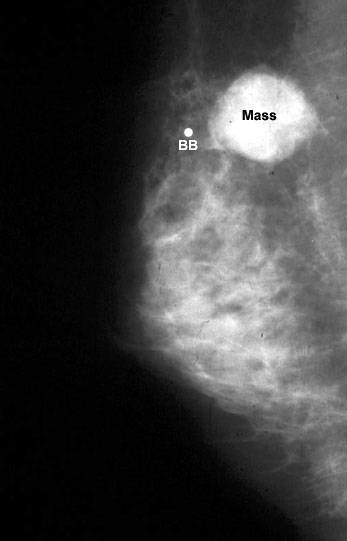

يمكن للعديد من حالات الثدي الحميدة أن تنتج كثافة متصاعدة قد لا يمكن تمييزها في التصوير الشعاعي للثدي عن السرطان.

تمت مصادفة كثافة الكتلة الموضحة في:

تندب ما بعد الخزعة

نخر الدهون المؤلم

خراج الثدي

التصلب الغدي…